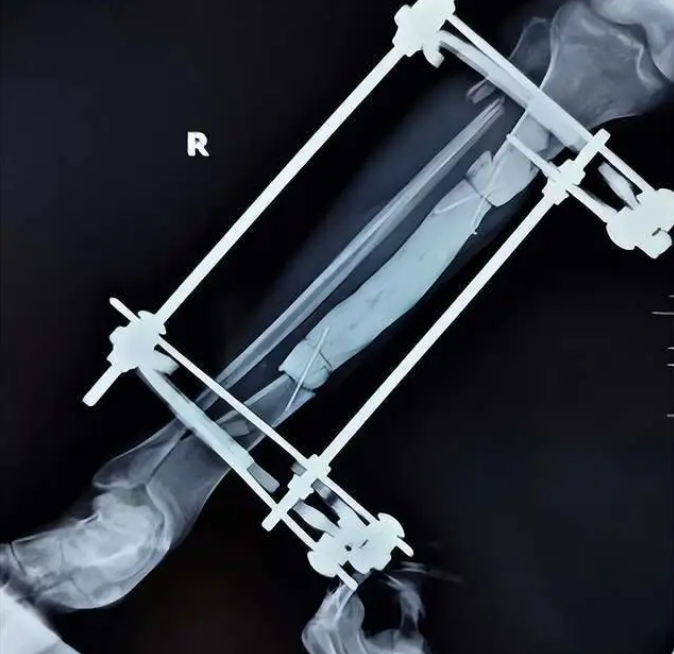

就诊后,接诊医生发现患者右小腿已存在严重感染,随即立刻安排急诊手术。术中发现患者右小腿大面积软组织缺损合并长节段胫骨骨外露,外露胫骨完全失活坏死,感染严重,异味明显。清理感染病灶及死骨后,进行骨感染早期骨水泥表面技术覆盖、负压引流术。

西安市红会医院阎良院区骨科创面修复团队,在主任医师宋涛的指导下,医生张世辉为患者制订了详细的手术方案。首先有效控制感染,之后进行二次清创手术。待各项指标稳定后,在麻醉团队的协助下,为患者进行骨水泥masquelet技术+游离股前外侧皮瓣覆盖创面,手术顺利完成。